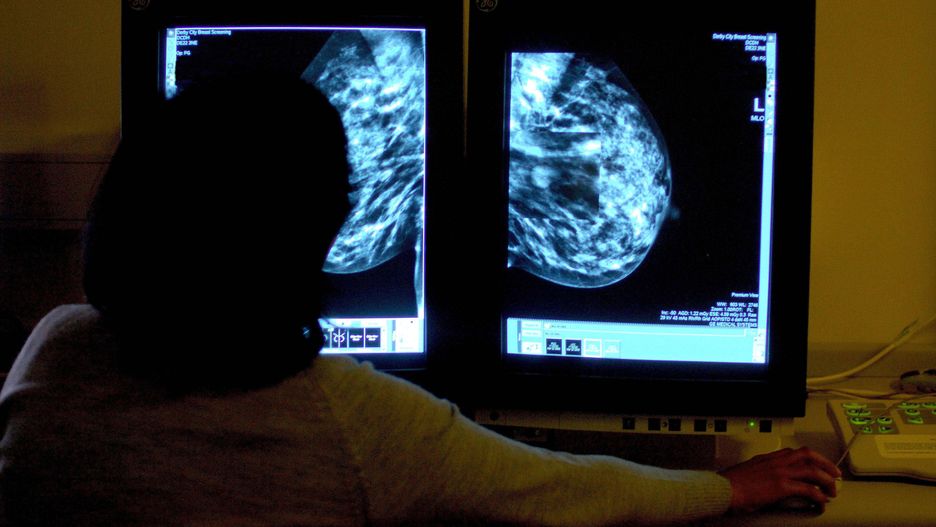

Dzielnica Wilanów zaprasza na bezpłatne badania mammograficzne. Wykryty we wczesnym stadium nowotwór daje szansę na całkowite wyleczenie.

- Zapraszamy Panie od 50 do 69 roku życia do skorzystania z bezpłatnych badań mammograficznych. Prowadzone będą w środę 2 września i w czwartek 8 października w godz. 9-17 na parkingu przy ul. Przyczółkowej 27A - w specjalnie zaprojektowanym Mammobusie. Został on wyposażony we wszystkie najważniejsze sprzęty do przeprowadzenia szczegółowego badania – przekazał Urząd Dzielnicy Wilanów.

Rak piersi w początkowym okresie rozwoju przebiega najczęściej bezobjawowo i zmiany nowotworowe w większości przypadków wykrywane są podczas profilaktycznej mammografii, lub innego badania diagnostycznego piersi. Dlatego tak bardzo ważna jest diagnostyka.

Mammografia to radiologiczna metoda badania piersi u kobiet. Wykonanie serii zdjęć przy użyciu promieni rentgenowskich pozwala na wczesne rozpoznanie choroby nowotworowej oraz innych nieprawidłowości, zanim pojawią się odczuwalne dolegliwości.

- Statystyki są porażające. Rak piersi to najczęściej występujący nowotwór u kobiet. Szacuje się, że zachoruje na niego aż jedna na dziesięć Pań. Ryzyko to wzrasta wraz z wiekiem. Dlatego zachęcamy mieszkanki Wilanowa do zadbania o swoje zdrowie i skorzystania z wizyty w Mammobusie – dodał Bartosz Wiśniakowski, zastępca burmistrza dzielnicy.